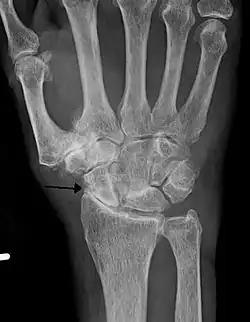

Lateral X-ray scan of ankle with secondary osteoarthritis

Lateral

Frontal X-ray scan of ankle with secondary osteoarthritis

Frontal

Secondary osteoarthritis of the ankle (due to an old bone fracture) in an 82-year-old woman